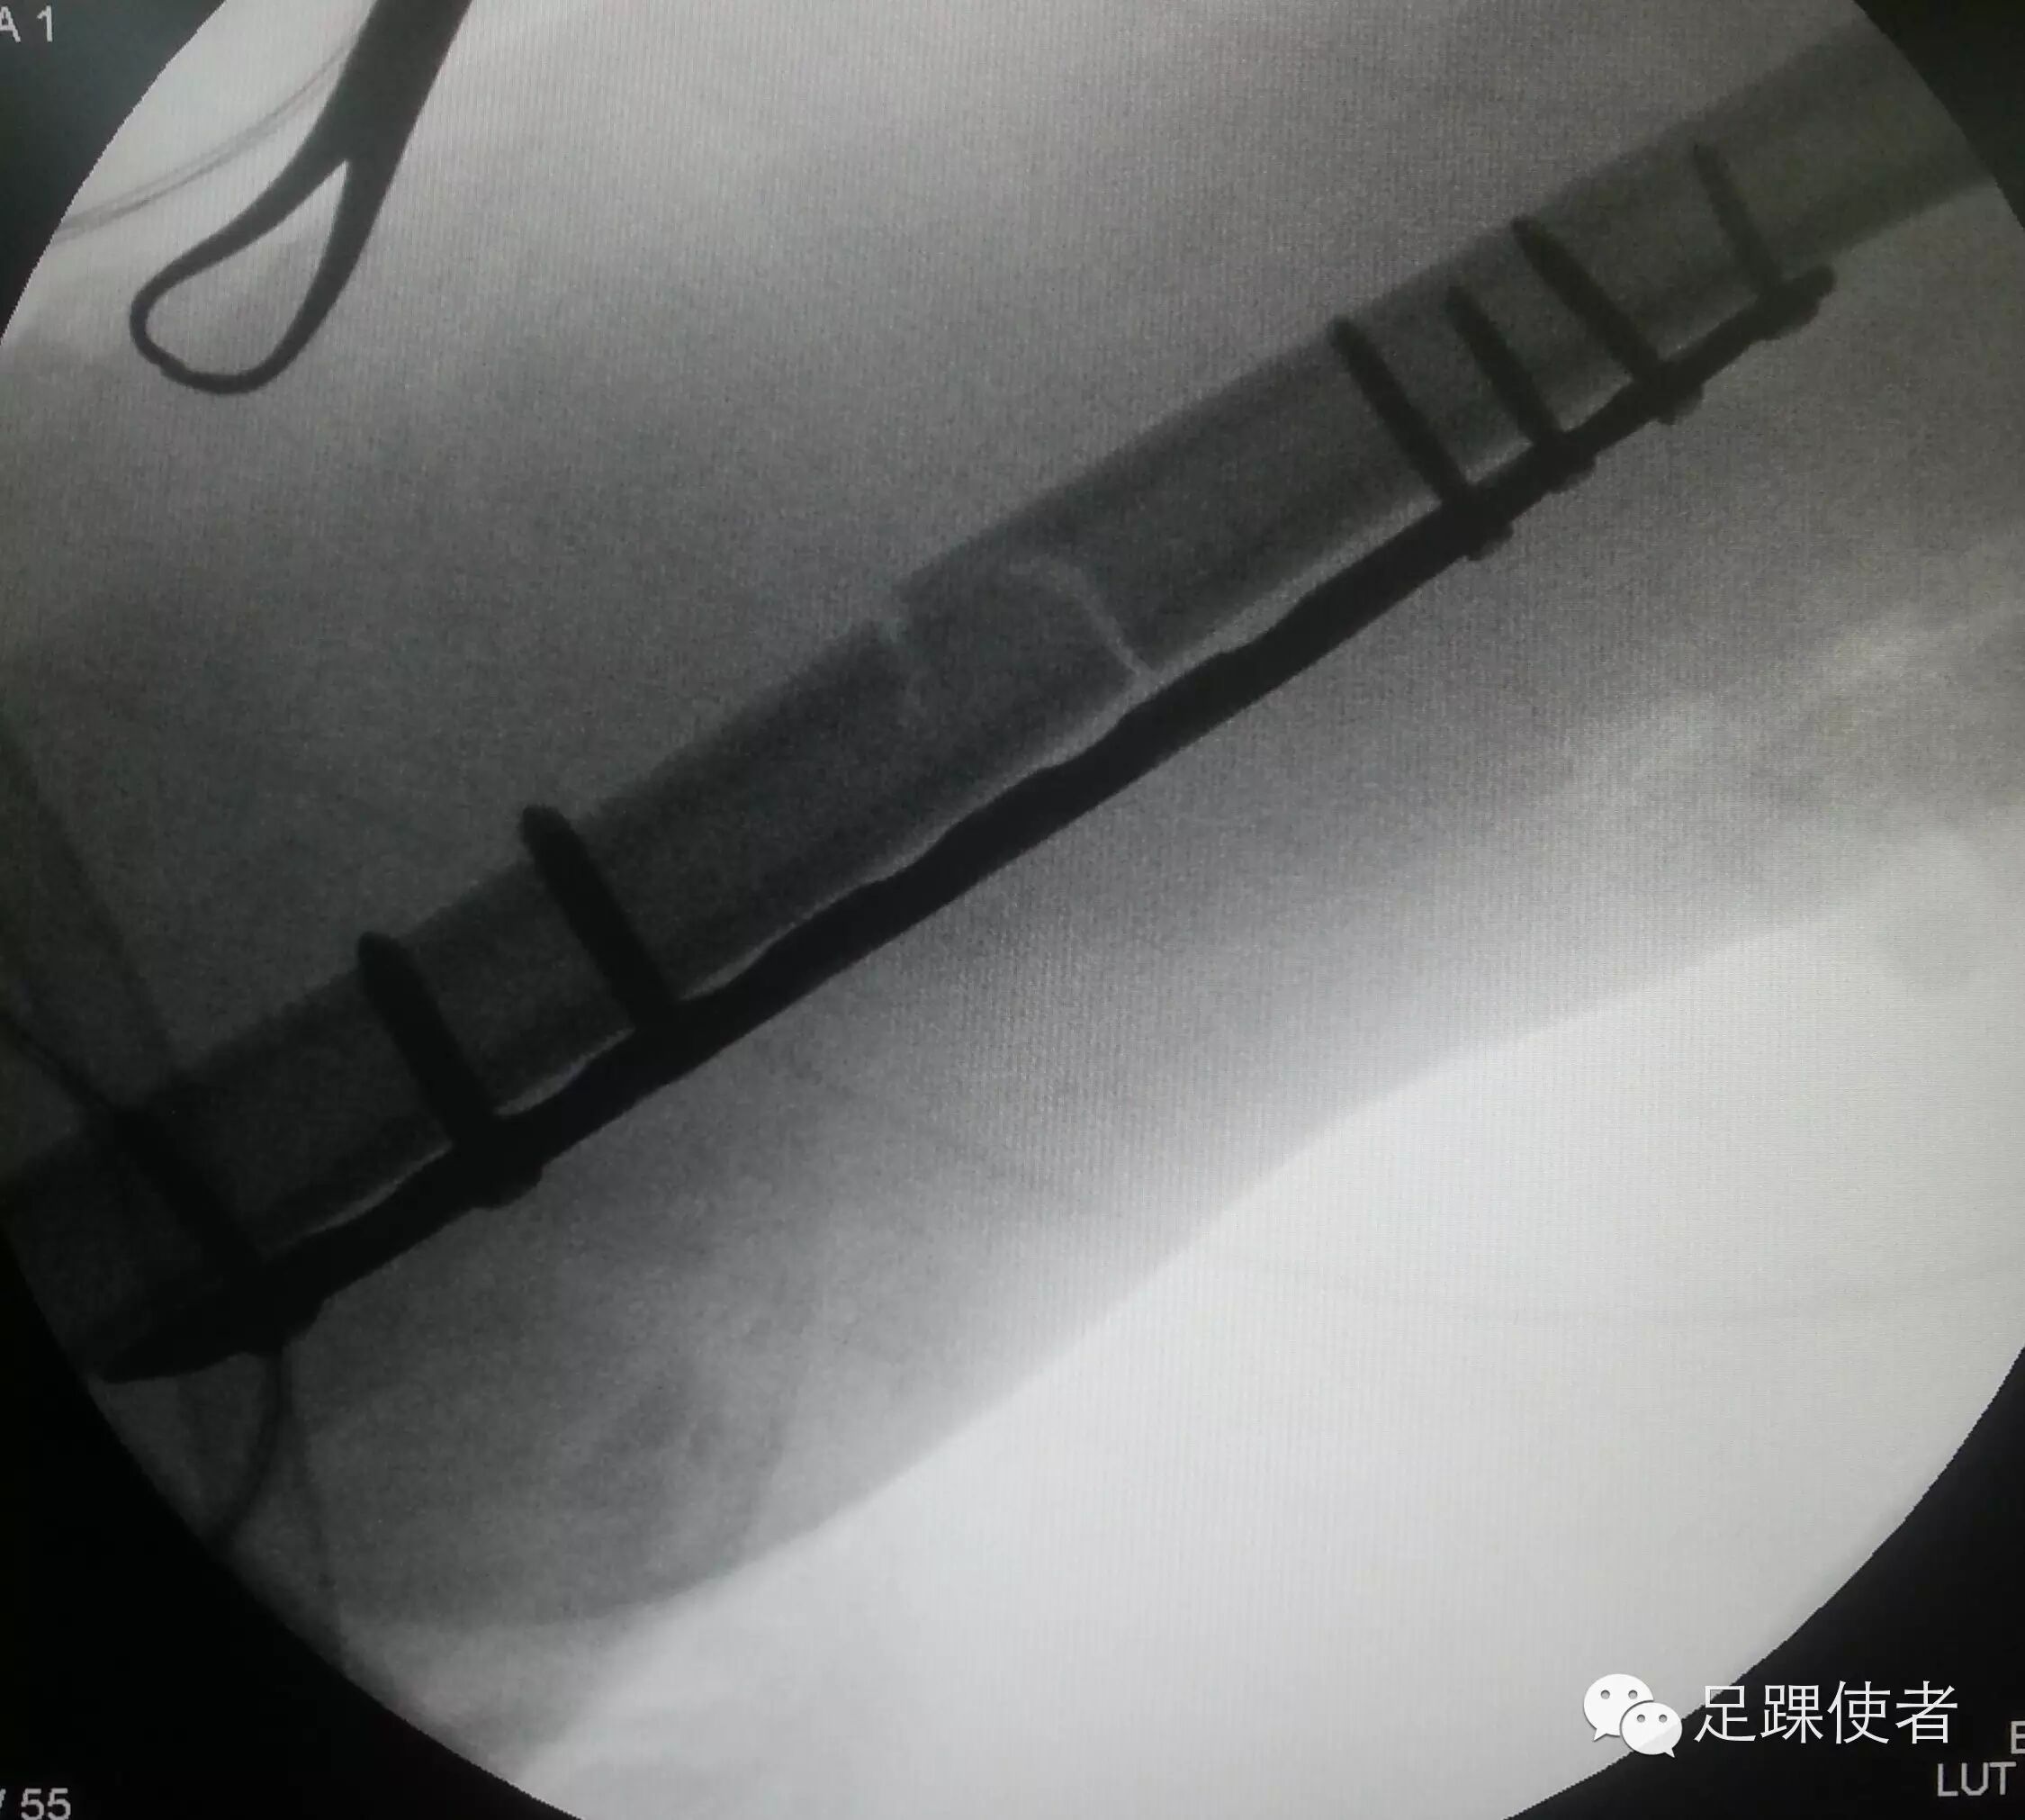

现在我们开展了微创治疗肱骨干骨折的新方法,只需经过两个小切口就可以复位骨折,并且放入一枚很长的钢板。即可靠地固定了骨折,又减小了组织损伤。